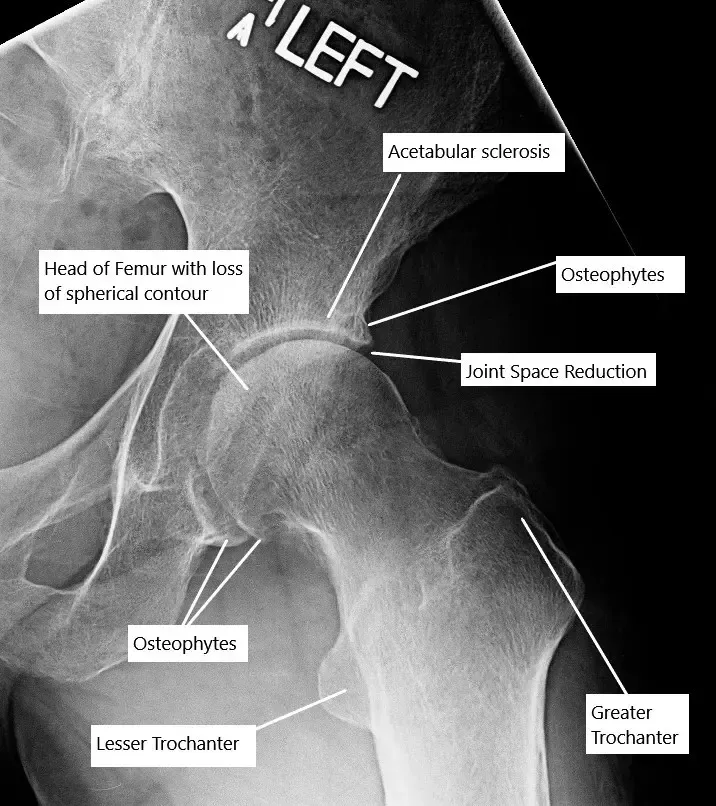

In the early stage of osteoarthritis, there is swelling of the articular cartilage, there is the appearance of fissures and cracks in the articular cartilage. The body attempts to repair it by increasing blood supply with the formation of new blood vessels. The new blood vessels invade the subchondral bone which leads to its increased density.

The destruction of the cartilage continues leading to decreased joint space visible on radiographs of large joints. The degenerated cartilage either dissolves in the joint or forms ‘’loose bodies’’ inside the joint. T

he body tries to repair the exposed bone resulting from the denuded cartilage. The repair leads to thickening and overgrowth of the subchondral bone. The thickening of the subchondral bone is especially prominent at the sides of the joint which appear as bone spurs.

The synovial membrane of the joint undergoes hyperplasia, which is swollen and inflamed. There is a development of cysts/cavities in the subchondral bone at the places of maximum stress. The pressure inside the joint increases as a result of decreased venous outflow and an increased arterial flow in the subchondral region. The increased pressure leads to the symptoms of pain at rest.

Plain radiographs are usually the first radiological test done to look for joint space reduction, cysts, and thickening bones. In some cases, for a detailed evaluation, a CT scan or an MRI may be ordered. An MRI gives the details of all the soft tissue structures inside the joint, which are not visible on an X-ray.